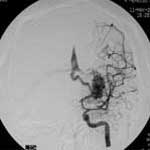

四.硬脑膜动静脉瘘(AVF)

----硬脑膜AVF是一种极复杂的颅内血管病,其分型方法可根据静脉引流的方式为:硬膜窦型、皮层静脉型、硬脑膜窦至皮 层静脉型、硬膜下静脉湖型、脊髓静脉型。也可以根据瘘口发生部分为:海绵窦区,横窦乙状窦区、窦汇区、上矢状窦 区、颅底区。栓塞治疗方法须根据分型而定,原则上是以永久性栓塞剂闭塞瘘口。单纯行瘘口孤立术,既创伤大,又难以 彻底解决问题,一支支供血动脉的栓塞,则此起彼伏,诸多侧支循环,十分棘手。通过对引流静脉血液动力学分析,针对 静脉窦的"竞争性血流",可以采取静脉窦闭塞的方法,从根本上解决多发性瘘口,在这方面一系列的血液动力学、影像解 剖学以及胚胎学的研究对治疗难治性脑膜动静脉瘘均有重要意义。